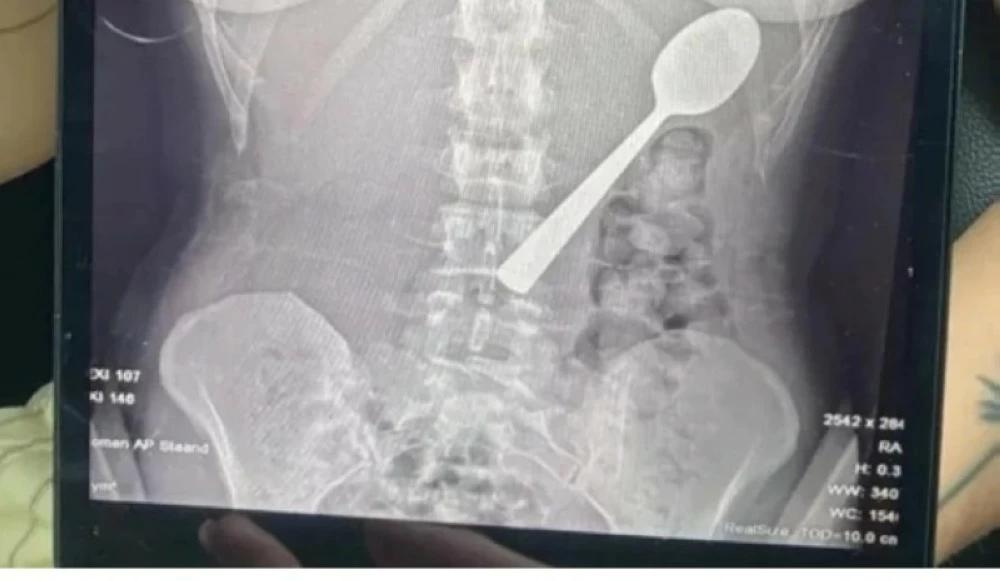

تحولت لحظة عشاء هادئة في منزل بلجيكي إلى أزمة طبية نادرة، عندما ابتلعت شابة تدعى ريمي أملينكس (28 عامًا) ملعقة بطول 17 سنتيمتراً. حدث ذلك بعد أن قفز كلبها من فصيلة “الهنغاريان فيزلا” على جسدها فجأة أثناء تناولها الزبادي، مما أدى إلى انزلاق الملعقة داخل حلقها.

اختارت ريمي الصمت عن الحادث، ولم تخبر شريكها عندما عاد من العمل، لكنها شعرت بالغثيان وآلامًا في البطن بسبب وجود الجسم الغريب. بعد يومين من المعاناة، زارت الأطباء، الذين صدموها بأن الملعقة أكبر من أن تمر عبر الجهاز الهضمي بشكل طبيعي.

خضعت ريمي لعملية منظار معدة تحت التخدير الموضعية، حيث تمكن الأطباء من سحب الملعقة بعد تدويرها بعناية. ورغم تعرضها لنزيف طفيف، لم تتعرض لأي مضاعفات دائمة. قررت ريمي الاحتفاظ بالملعقة كذكرى من هذه الواقعة الغريبة، فيما يخطط شريكها لتحويلها إلى قطعة فنية. أثارت القصة تفاعلاً واسعاً على وسائل التواصل الاجتماعي، متطرقة لمخاطر الأجسام الغريبة والحوادث المنزلية المفاجئة.